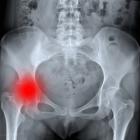

Когда подходит время, гинеколог назначает УЗИ для того, чтобы определить количество плодов и их расположение. Выявить количество плодов при помощи современного оборудования можно достаточно легко. Уже на 5й неделе отчетливо прослеживаются два отдельных плода, которые могут быть разделены перегородкой или нет. Зачастую подобное обследование проводится при помощи специализированного оборудования влагалищным датчиком.

Всем беременным женщинам, вынашивающим двоих или более плодов, показано УЗИ в период примерно с 10 по 13 неделю. Это делают для того, чтобы определить жизнеспособность и количество плодов, наличие врожденных пороков и прочих особенностей. При протекании многоплодной беременности внутренние органы женщины страдают в значительной степени, поэтому для нее крайне важно проходить своевременное и регулярное обследование.